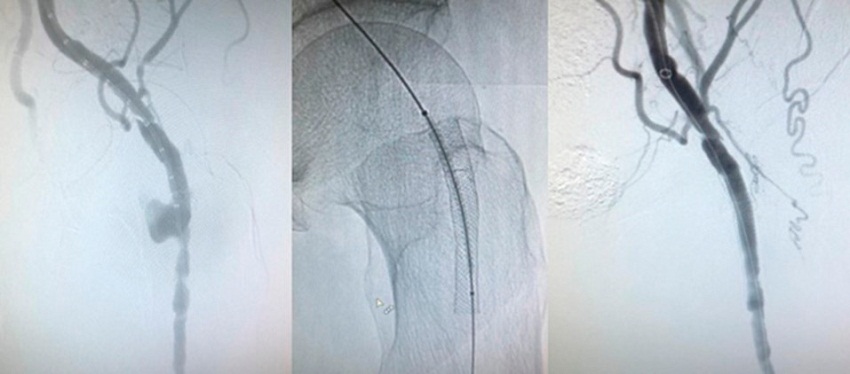

Al noveno día presentó súbitamente hipotensión arterial y dolor en fosa ilíaca izquierda, asociado a caída de 8 puntos del hematocrito. La angiotomografia evidenció ruptura contenida de pseudoaneurisma de arteria femoral común izquierda, a nivel del sitio de implantación del wallstent, con hematoma retroperitoneal de 15 × 7,5 cm. (Figura 1) De urgencia, por acceso percutáneo femoral contralateral, se procedió a implantar stent graft auto expandible (Viabahn®) de 7 × 50 mm, por dentro del wallstent que se encontraba permeable e indemne, con evidencia de extravasación de contraste por ruptura de la pared arterial. (Figura 2) El paciente evolucionó afebril, con hemocultivos negativos y eco Doppler cardíaco sin vegetaciones; cumplió 15 días de tratamiento antibiótico endovenoso y luego recibió ciprofloxacina 750 mg c/12 horas vía oral hasta completar 6 meses. Se encuentra asintomático en el seguimiento a 2 años.